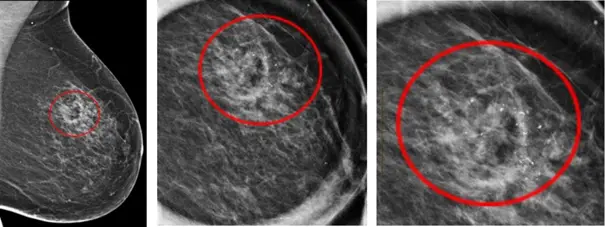

Le radiologue est particulièrement attentif à rechercher des opacités (nodules), des troubles de l’architecture glandulaire ou des microcalcifications.

Ces dernières sont très fréquentes et très majoritairement bénignes mais plus suspectes de cancer du sein si elles sont groupées et irrégulières.

Foyer de microcalcification découvert par le radiologue et mieux caractérisé sur des clichés d’agrandissement.